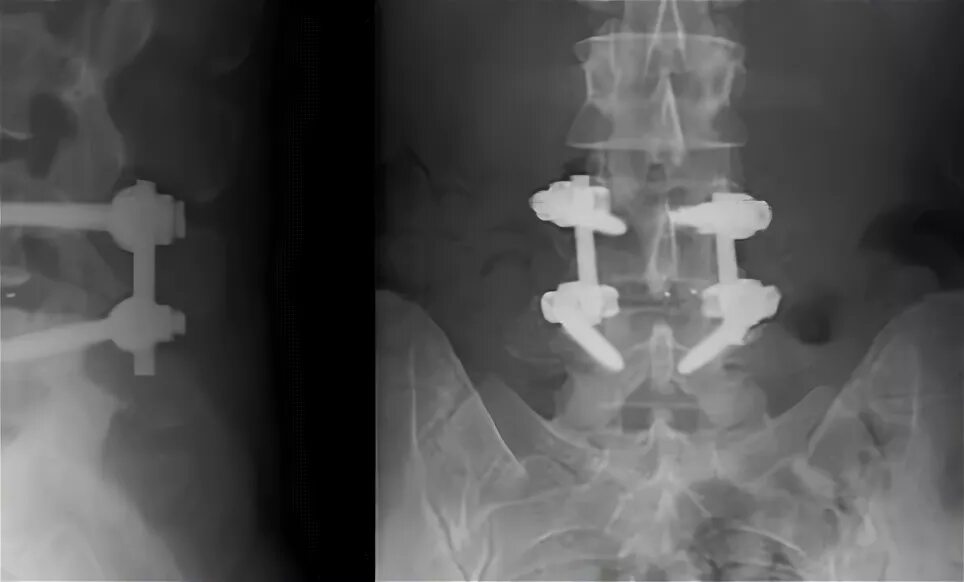

Диффузная грыжа l4 l5